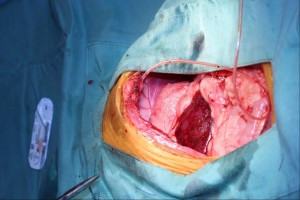

術中の写真

皮膚はサージカルマージンとして約3cmを確保しました。その後、筋膜のマージンも同様に確保するために縫合しにてマーキングしながら筋切開を実施しました。